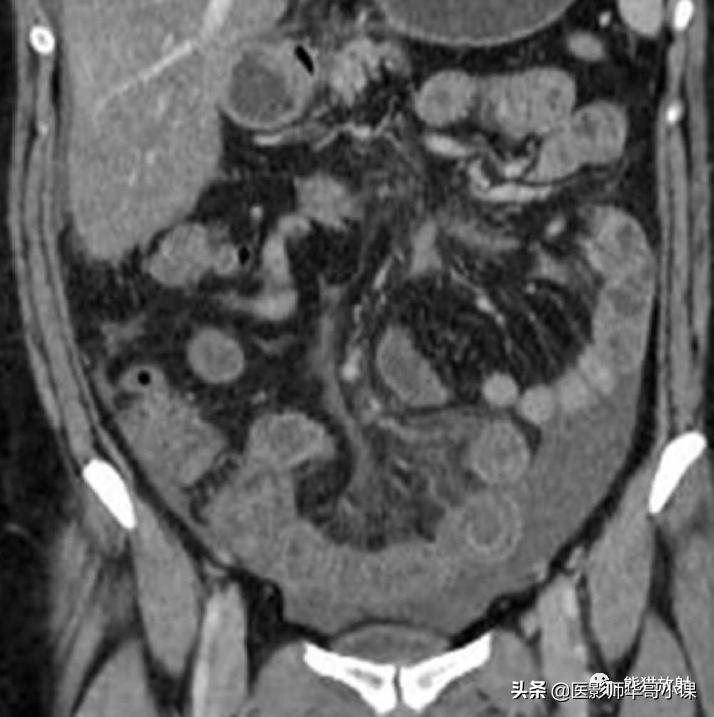

亦称作腹膜硬化症,是一种罕见的腹膜慢性炎症性疾病, 主要发生于持续非卧床腹膜透析患者, 这类患者的发病率和病死率都很高。其他的少见病因包括腹部结核、复发性腹膜炎、长期使用β受体阻滞药(普萘洛尔/心得宁)、结节病等。患者可以没有症状,或者出现恶心、食欲减退、营养不良、体重减轻和反复发作的小肠梗阻。

CT是硬化性腹膜炎的最佳检查手段。腹膜均匀或不规则结节状增厚、钙化,腹膜明显强化,包裹性积液,束缚状厚壁肠襻是本病的 特征性CT表现 (图)。

硬化性腹膜炎。增强CT显示包裹积液及腹膜广泛钙化